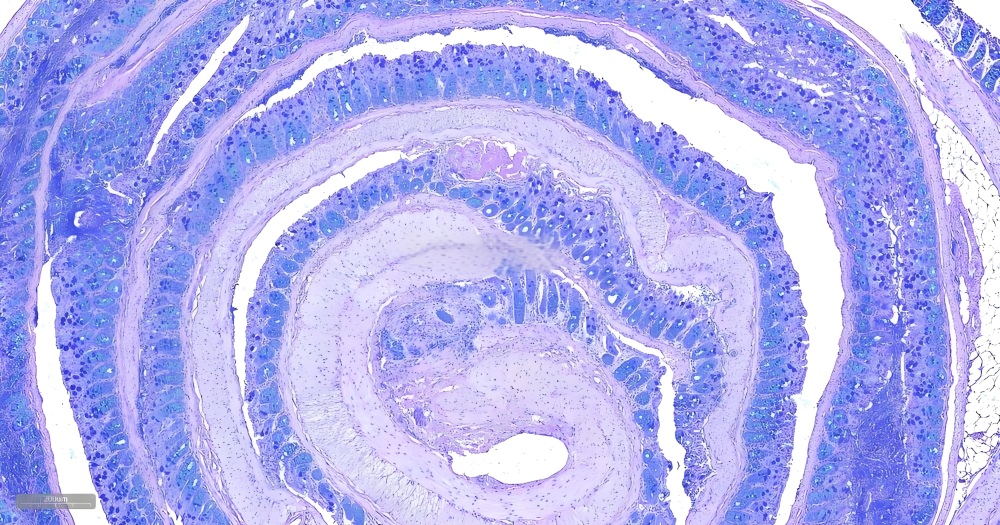

AB-PAS(阿尔新蓝-过碘酸雪夫)染色是一种组织化学联合染色技术,通过阿尔新蓝(Alcian Blue)特异性标记酸性粘多糖(如硫酸化粘蛋白),并利用PAS(Periodic Acid-Schiff)反应检测中性粘液物质(如糖原、糖蛋白),实现在同一张切片上区分两类重要碳水化合物成分。该技术具有高对比度(酸性粘液呈蓝色,中性粘液呈紫红色)和病理诊断价值,广泛应用于胃肠道杯状细胞分型、呼吸道粘液分泌评估及肿瘤微环境研究,尤其对黏液性肿瘤(如卵巢黏液性癌)的鉴别诊断至关重要。

酸性粘液物质:蓝色。

中性粘液物质和糖原:红色或紫红色。

细胞核:蓝色(苏木素复染)或红色(核固红复染)。

相较于单一染色技术(如PAS染色或阿尔辛蓝染色),AB-PAS染色可同时检测酸性粘液和中性粘液,提供更全面的组织化学信息,尤其适用于复杂样本的分析。